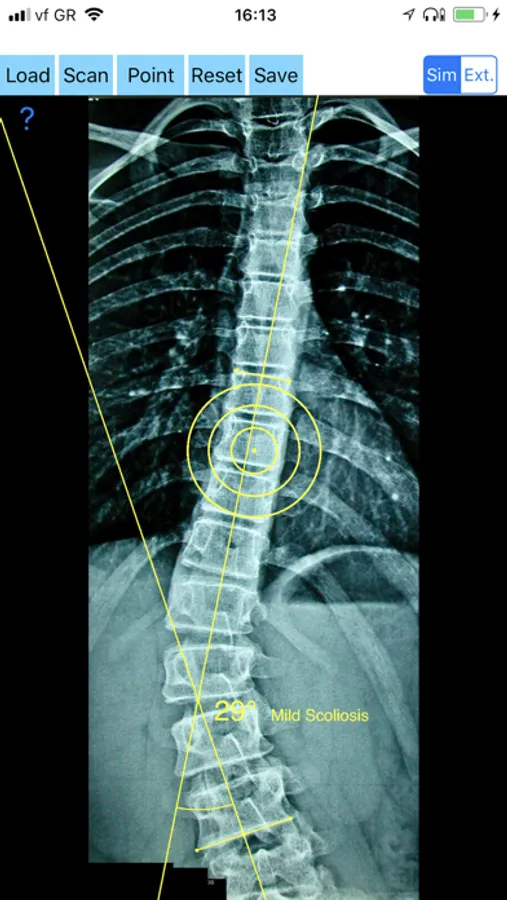

-Offers a very convenient way to determine the most accurate possibly way at once. By marking four points at the same X-ray, at each spine the App calculates the Cobb angle. In cases where values are out of normal ranges, the scoliosis is categorized according to measured angle as mild, moderate, severe. To simplify the process and to minimize inter-observer errors usually by not selecting the actual end vertebra, the app offers also in ext mode the ability to draw the vertical reference line through the patient’s sacrum and to identify more easily the end vertebrae s (ext method).

CobbAngleApp Screenshots